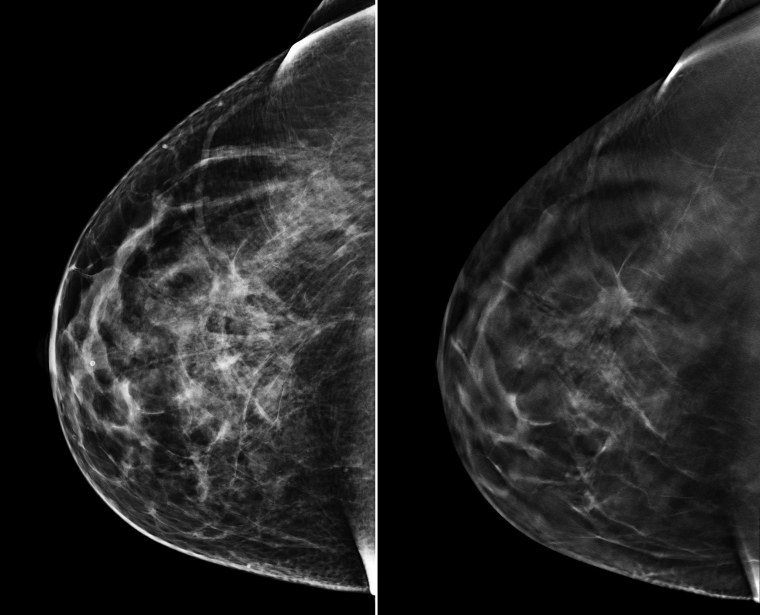

Что такое маммография: важность, процесс и результаты